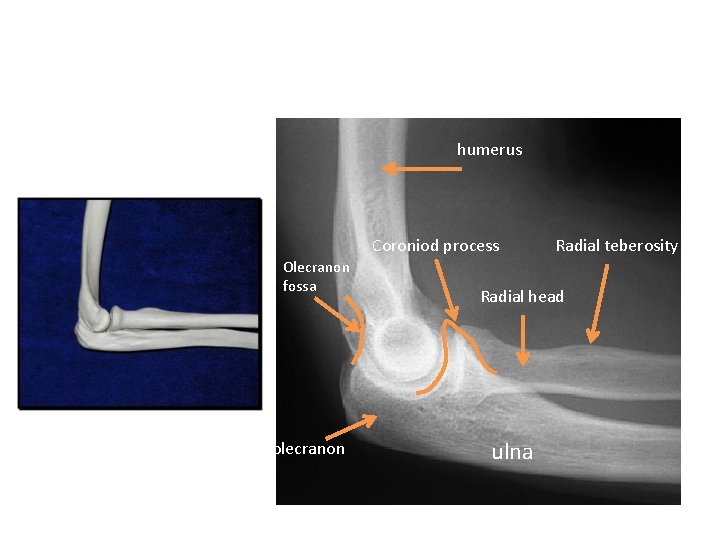

ELBOW

X RAY

humerus Coroniod process Olecranon fossa olecranon Radial teberosity Radial head ulna